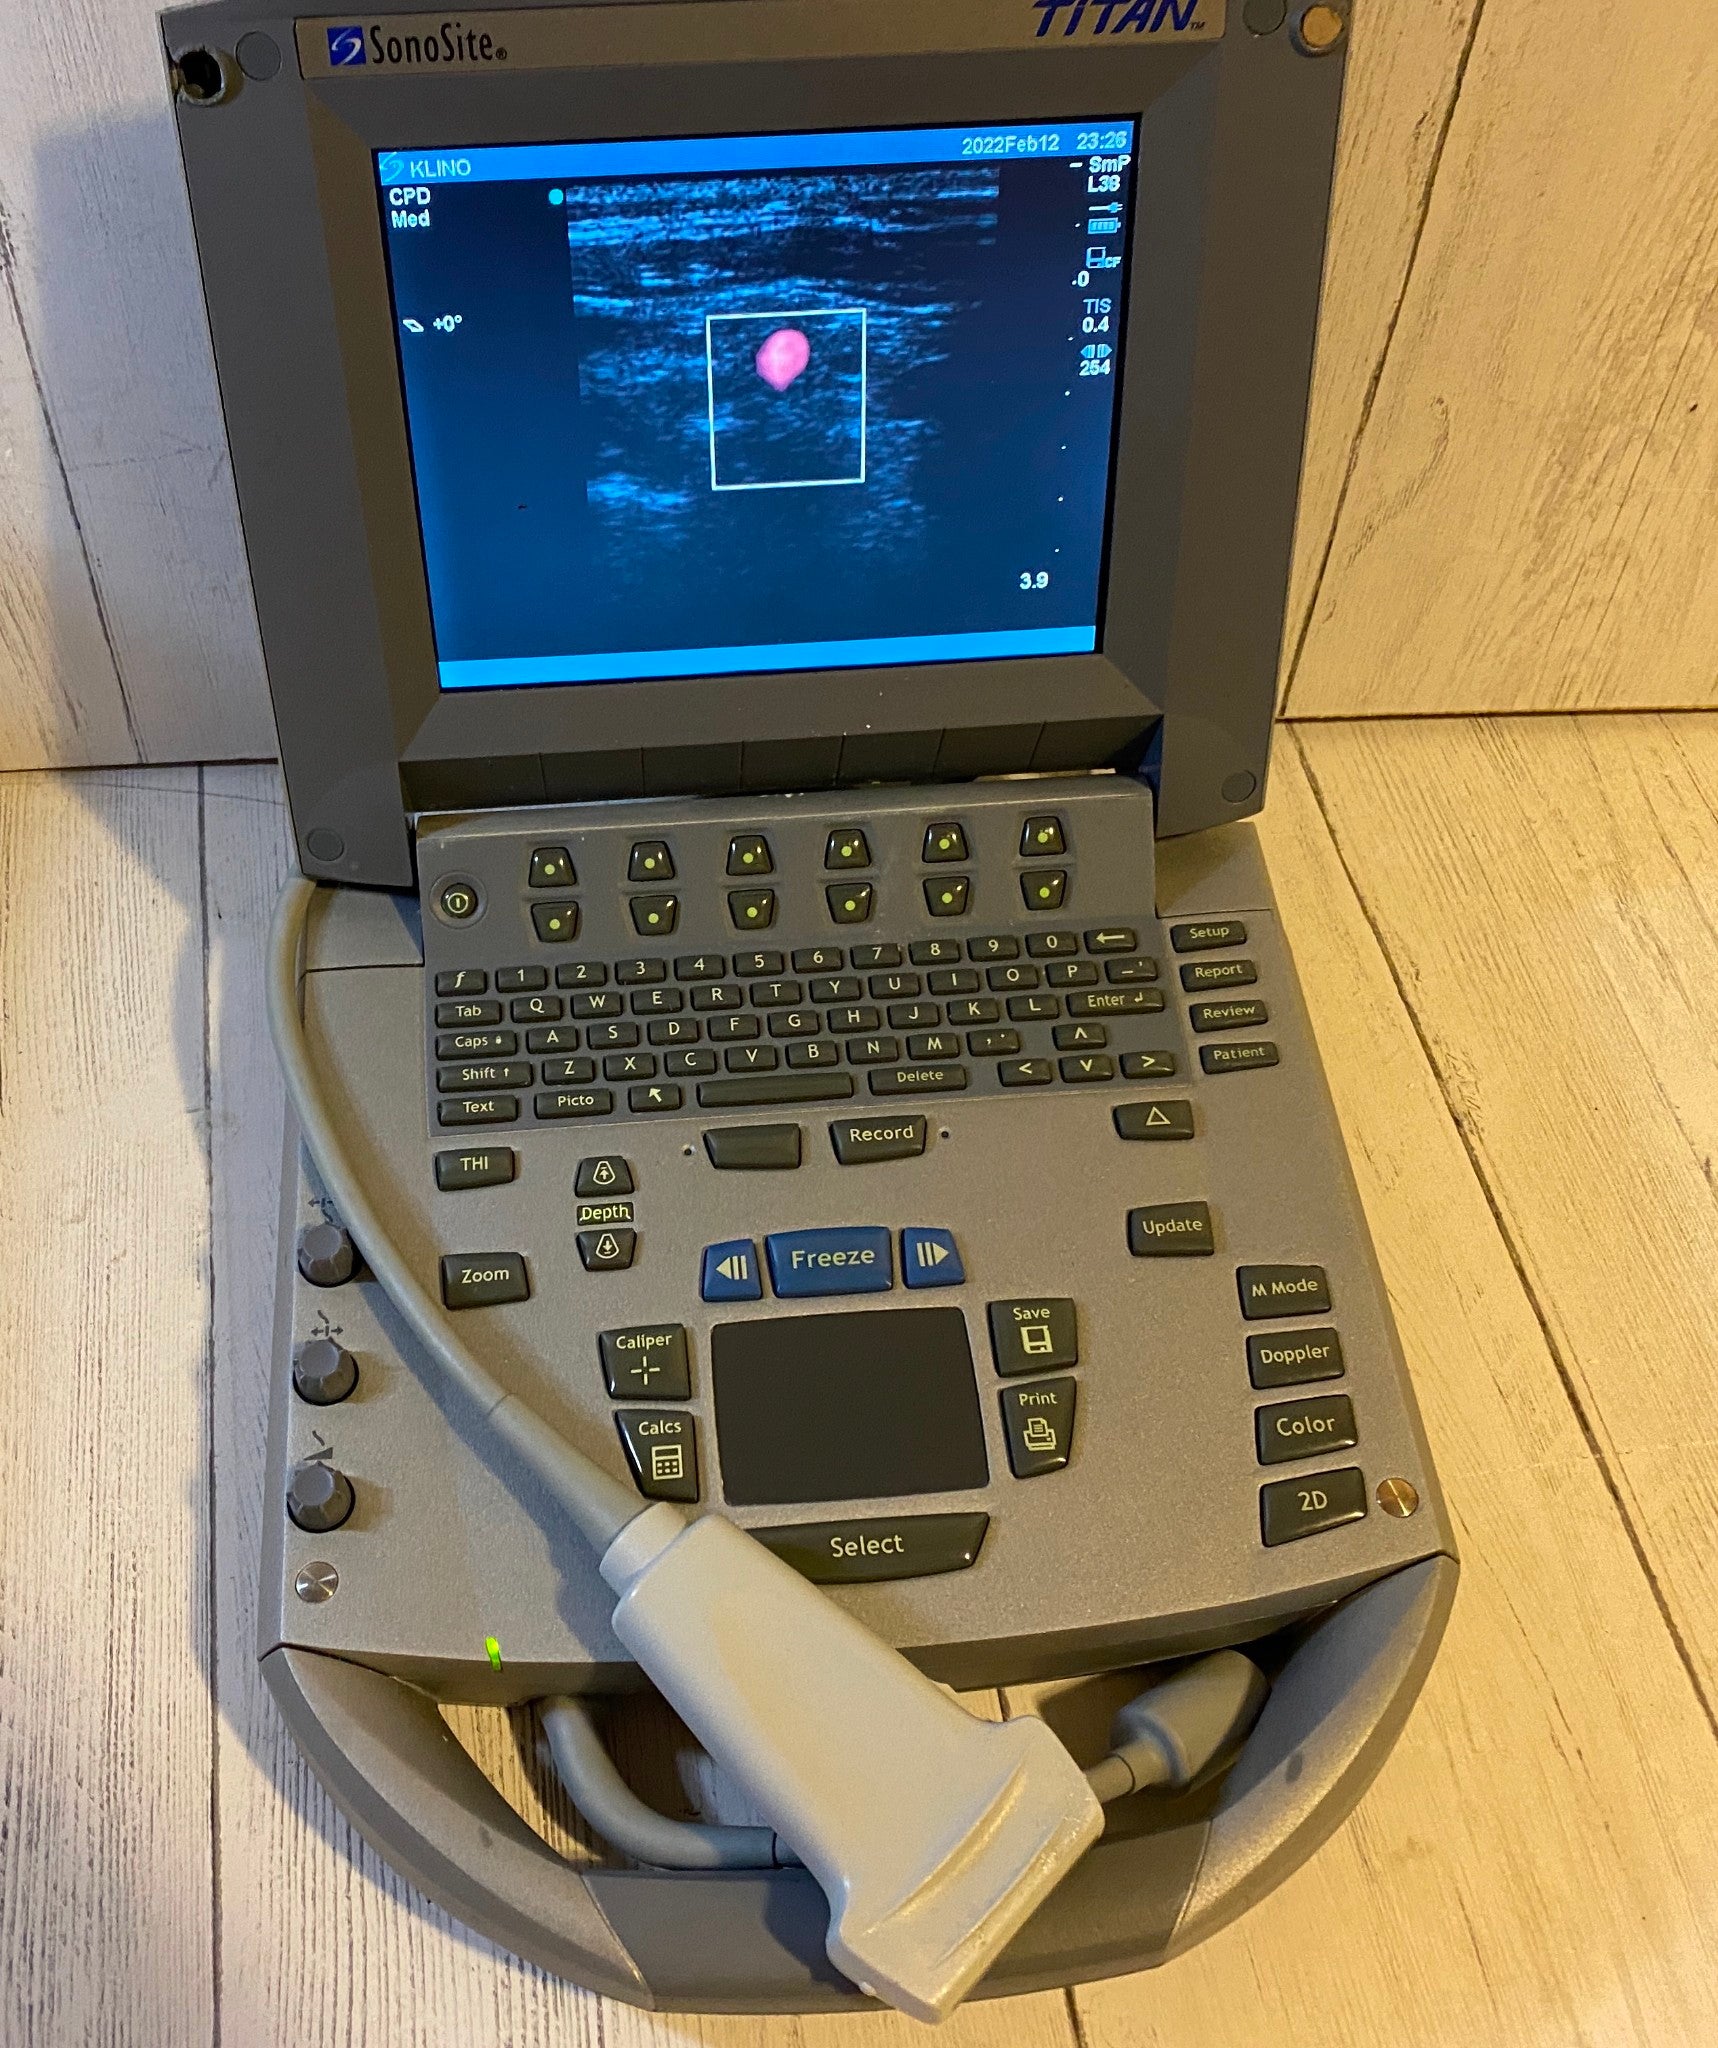

DIAGNOSTIC ULTRASOUND MACHINES FOR SALE